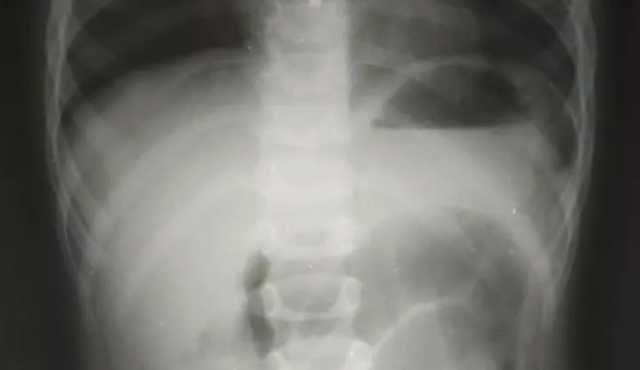

Дитячого хірурга Кирила Лапшина дуже здивував рентген-знімок. У черевній порожнині чітко візуалізувався дивний сторонній предмет, який за обрисами схожий на кулю від пневматичної гвинтівки. Медик уточнив у тата хлопчика, чи міг син проковтнути кулю.

Чоловік повідомив, що у них вдома є пневматична рушниця та до неї металеві кулі, якими дитина нещодавно гралася. Ймовірно, випадково хлопчик проковтнув одну з них.

Все б закінчилося добре, якби куля потрапила зі шлунка в кишківник і вийшла. Але в маленького пацієнта куля потрапила в апендикс, це стало причиною запального процесу, через що хлопчику знадобилася термінова операція. Хворому провели лапароскопічну операцію — видалили запалений апендикс через три невеликі проколи у животі. «Коли ми видаляли апендикс, я відразу побачив, що в ньому є потовщення. Ми його видалили й уже назовні розрізали.

Там справді була куля! Вона, як стороннє тіло, потрапила з кишківника в апендикс і створила його обструкцію. Це і стало незвичайною причиною апендициту», — повідомив дитячий хірург Кирило Лапшин. Малечу вже виписали додому, а його батько пообіцяв медикам надійно ховати кулі та зброю.